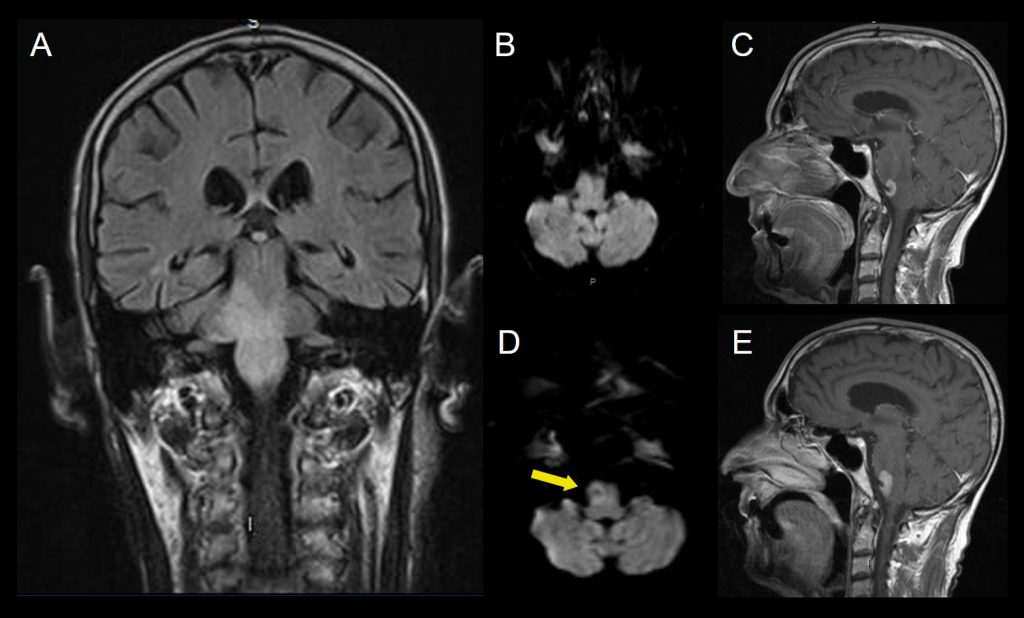

A. FLAIR coronal

B.Difusión axial. Alteración de señal bulbo protuberancial de predominio del lado derecho, que se extiende al pedúnculo cerebeloso, sin restricción a la difusión.

C. T1+Gd sagital. Foco de realce bulbar anterolateral derecho.

25 días después se realiza nueva RM que muestra

D. Difusión axial. Restricción a la difusión en las lesiones bulbo protuberanciales (flecha amarilla).

E. T1+Gd sagital. Mayor realce en las secuencias con contraste.